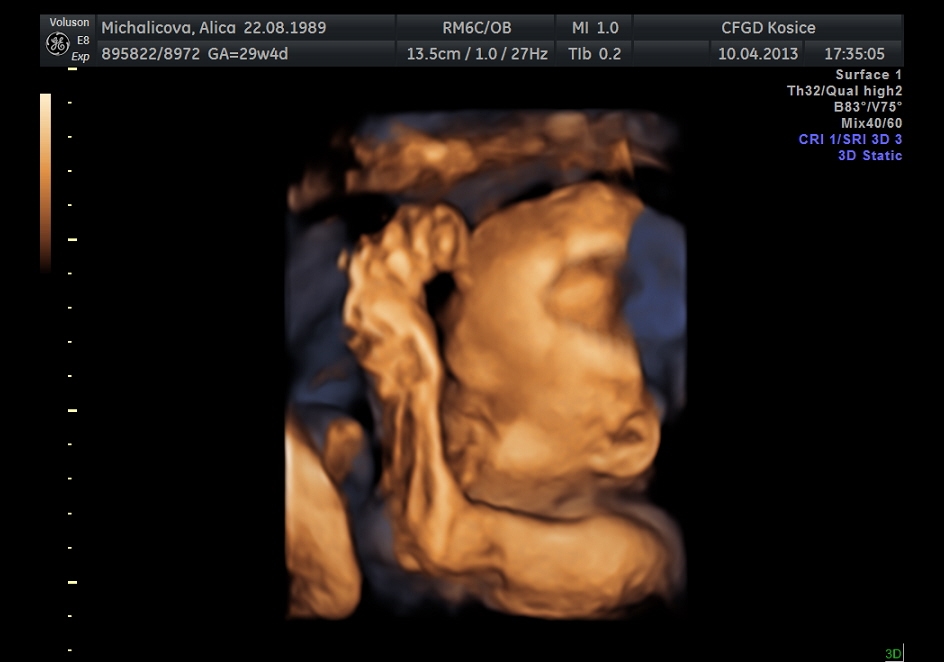

ahojte baby, tak máme za sebou 3D ultrazvuk som sa tešila že uvidim tváričku malej ale potvorka sa celý čas zakrývala ručkami tak vela toho nevidno 😀 ale nevadí no, hlavne že je všetko v poriadku má okolo 1550g... nezdá sa vám to vela na 30.tt?neviem to porovnať lebo pri prvej dcerke som nebola na 3D. Pekný dník prajem ešte pridám 2 fotky :o)